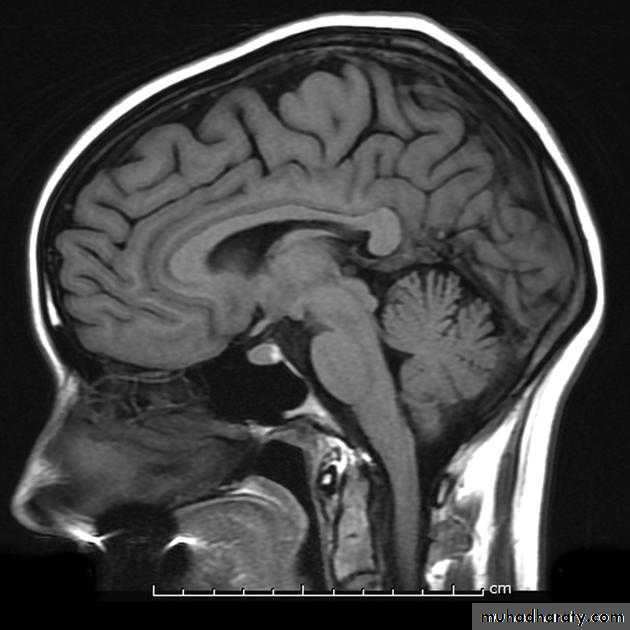

MRI is the investigation of choice for imaging of the pituitary gland and adjacent structures.

• Sagittal T1-weighted images demonstrate the lobar anatomy of the pituitary:

• Adenohypophysis of similar signal intensity to brain tissue

• Neurohypophysis seen as a posterior ‘bright spot’.

• Coronal T1-weighted scans with dynamic contrast enhancement are particularly useful for the diagnosis of microadenomas. Where MRI is unavailable or contraindicated CT may be used, however it is much less sensitive.